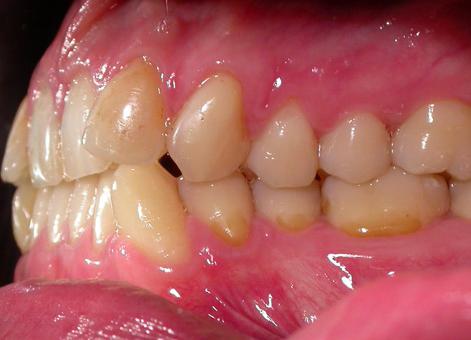

Пациент обратился с диагнозом индивидуальная макродентия.

Диагностика дополнительно выявила:- тенденцию к формированию мезиальной окклюзии,

- сужение и укорочение зубных рядов,

- ретрузию верхних центральных резцов,

- мезиальное смещение боковых отделов нижнего зубного ряда,

- ретрузию нижних резцов,

- множественные аномалии положения зубов.